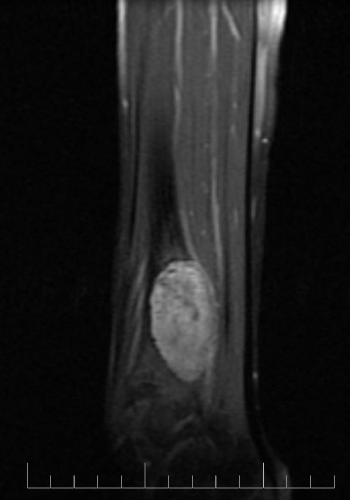

A 10-year-old female presented with left lower leg pain that had progressively increased over the duration of 1 year. On physical examination, tenderness was elicited on palpation of the distal tibia. Routine laboratory testing was normal. X-Ray was performed and revealed a lytic lesion with sclerotic margins in the left lower tibia (Figure 1). MRI was subsequently performed, demonstrating a left lower tibia lesion with low signal intensity on T1 weighted images (Figure 2), and high signal intensity on T2 weighted images (Figure 3). Pathology of the tumor revealed a diagnosis of a CMF. She was treated with curettage and autologous bone grafting (Figure 4). Post op eratively the left leg was immobilized with a plaster cast with restricted weight bearing (Figure 5). Follow up X-ray after 5 years demonstrates no tumor reoccurrence (Figure 6, Figure 7).

Figure 2: MRI sagittal T1 of the left tibia.

MRI demonstrates low signal intensity on T1 weighted images (Figure 2, Figure 11 and Figure 12). T2 weighted images demonstrate high signal intensity (Figure 3, Figure 13). Post gadolinium contrast T1 weighted sagittal view demonstrates diffuse heterogenous enhancement (Figure 14). Post gadolinium contrast T1 weighted axial view demonstrates peripheral nodular enhancement (Figure 15).